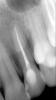

Camomile Опубликовано 29 июня, 2010 Поделиться Опубликовано 29 июня, 2010 Добрый вечер.Подскажите, пожалуйста, почему у меня ноет 2 верхний зуб? 4 месяца назад в нем был запломбирован канал и удален нерв. После лечения зуб побаливал, врач сказала, что это нормально, потому что зубы чувствительные. Со временем боль практически пропала. Неделю назад были запломбированы каналы в 5 верхнем зубе и после этого 2 верхний зуб стал ныть, на него больно нажимать у основания. Сегодня снова сделали снимок второго верхнего зуба. Стоматолог сказала, что он здоровый и возможно в него отдает 5 зуб (пролеченный неделю назад) или же в 1 зубе пульпит, хотя там лечили кариес. Права ли стоматолог? Может зуб полечить лазером или он плохо пролечен и его нужно перелечивать? Надеюсь на помощь, спасибо. Снимки прилагаю. Ссылка на комментарий